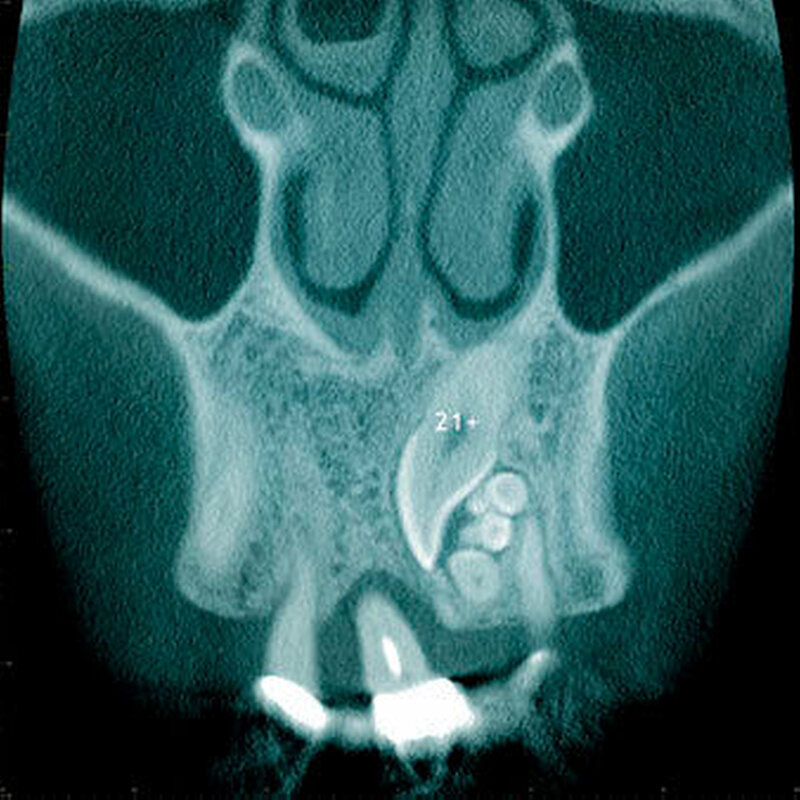

Radiologisch erscheint der Zahnfollikel um retinierte überzählige Zähne als eine dünne perikoronale Radio-luzenz, welche in der Regel nicht breiter als 3 mm ist [Mossaz et al., 2014] (Abbildung 19). Andere Autoren betrachten eine Breite von 2 mm als physiologisch [Tyrilogou et al., 2005]. Bis heute fehlen aber klare Angaben zu den normalen Dimensionen des Zahnfollikels, das heißt, es ist radiologisch nicht eindeutig zu erkennen, wann ein zystischer Prozess vorliegt [Villalba et al., 2012]. Studien berichteten über eine (pathologische) Erweiterung des Follikularraums in 1,4 Prozent bis 5,3 Prozent der überzähligen Zähne [von Arx 1990; Tyrologou et al., 2005; Liu et al., 2007; Hyun et al., 2009; Mossaz et al., 2014]. Dagegen sahen Koch und Mitarbeiter (1986) bei 54 überzähligen Zähnen keine Erweiterung des perikoronaren Raumes während des Beobachtungsintervalls (Mittelwert: 7,3 Jahre).

Der letzte Typ der überzähligen Zähne ist das Odontom. Obwohl das Odontom gemäß WHO-Klassifikation als odontogener Tumor eingeteilt wird [Praetorius Piatelli, 2005], sind sich heute die meisten Autoren darin einig, dass ein Odontom keine benige Neoplasie darstellt, sondern eine hamartomatöse Fehlbildung ist [Garvey et al., 1999; Wang Fan, 2011]. Beim Odontom können zudem klinisch-radiologisch sowie histologisch zwei Arten unterschieden werden: Das komplexe Odontom, bei welchem Zahnhartgewebe als diffuse Masse, das heißt gänzlich unorganisiert angelegt ist, und das zusammengesetzte Odontom, welches aus multiplen zahn- ähnlichen Strukturen besteht, die jeweils bindegewebig abgegrenzt sind.